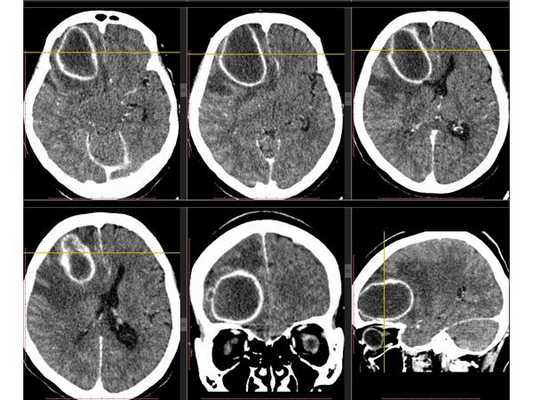

Рентгенография лёгких: без патологии. УЗИ органов брюшной полости: выявлены хронический холецистит, хронический панкреатит, диффузные изменения печени и поджелудочной железы. ЭКГ: в норме. На КТ головного мозга визуализировалось объёмное образование в правой лобной доли. Это вызвало подозрение на абсцесс, но отсутствие уровня жидкости, лихорадки и менингеального синдрома у пациентки в большей степени склонило клиническую мысль в сторону онкологического поражения. В связи с этим пациентку госпитализировали в отделении неврологии. Однако при осмотре онкологом и гинекологом данных, которые бы подтверждали наличие онкологии головного мозга, обнаружено не было. В качестве дообследования проведена КТ головного мозга с контрастным усилением. Она выявила объёмное образование в правой лобной доли с чётко очерченной капсулой. Рядом с образованием располагался отёк, срединные структуры были смещены влево примерно на 5 мм.

3D-реконструкция объёмного образования правой лобной доли головного мозга, выполненная на основании сканов КТ с контрастным усилением

Инкапсулированный абсцесс мозга на КТ имеет вид округлого объемного образования с четкими ровными контурами повышенной плотности (фиброзная капсула). В центре капсулы зона пониженной плотности (гной), по периферии видна зона отека. Введенное контрастное вещество накапливается в виде кольца (по контуру фиброзной капсулы) с небольшой прилежащей зоной глиоза.